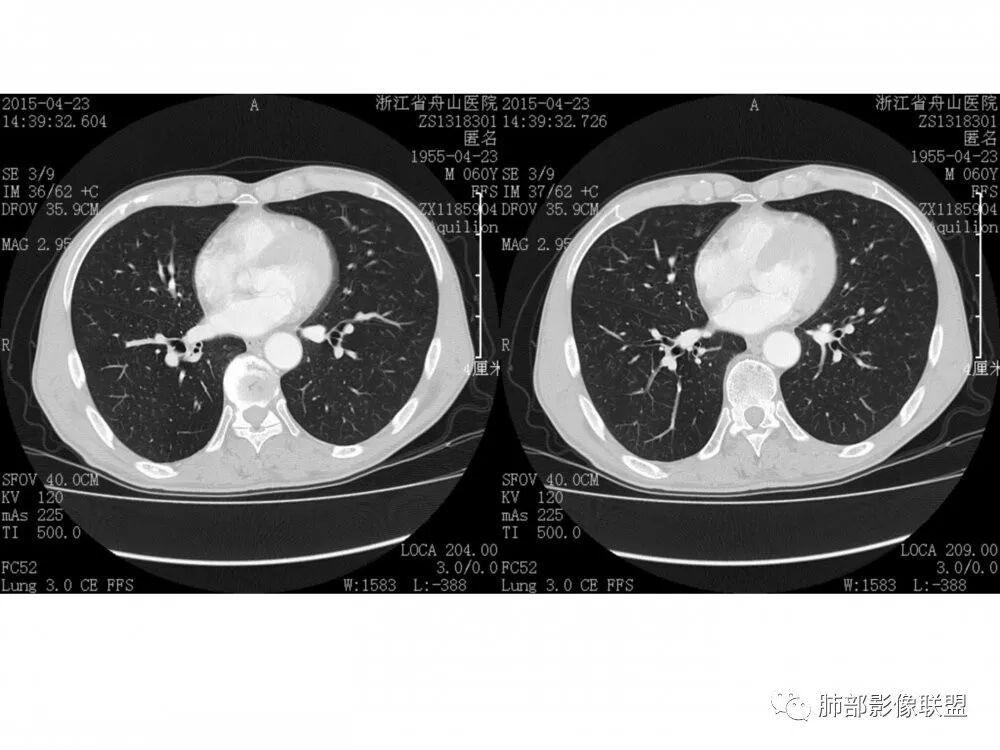

右肺下叶支气管不规则软组织肿块,病灶沿支气管生长,有一定的张力,部分包绕支气管壁,增强病灶内可见中度强化,内部有延迟强化的特点,周围淋巴结增大,诊断恶性病变无疑,远端无明显支气管阻塞,主要考虑粘液表皮癌,腺样囊腺癌,鳞癌之间鉴别,病灶有类似神经源性病变生长方式,腺样囊腺癌,其次考虑鳞癌或粘液表皮癌。

支持腺样囊性癌,老年男性,支气管肿块,横径大,轻度不均匀强化,小血管受侵模糊,纵隔肺门多发肿大淋巴结。代排黏液表皮癌,一般年轻人,强化更轻。鳞癌,无阻塞性肺炎不太支持,小细胞癌及不典型类癌放后面考虑

右肺门结节,内见包埋血管,不均匀强化,长轴沿支气管且围绕支气管生长,支气管受压狭窄而未阻塞,肺门及纵隔见肿大淋巴结,老年男性,似有肺气肿背景,考虑恶性肿瘤性病变,首选小细胞肺癌

右肺下叶支气管开口新生物,轴位管腔及纵向基底干大部分受累狭窄,支气管管壁破坏并突破形成腔外肿块,血管累及变细,肉眼观轻度强化,右肺门、纵膈淋巴结肿大,恶性没问题,阻塞性炎症不明显,类癌强化明显不支持,老年男性,首先考虑小细胞癌,鉴别不典型鳞癌和腺癌。

右肺下叶开口支气管内新生物,破坏管壁向腔外膨胀生长,累及各基底段开口,无明显坏死,有局部强化,远端无明显阻塞,右肺门及纵隔淋巴结肿大,考虑恶性肿瘤。大气道肿瘤不支持腺癌。小细胞癌大多为周围病灶引起肺门、纵隔淋巴结转移,肺门淋巴结明显肿大后侵犯支气管粘膜到达支气管内(从外到内),本例病灶从管腔内向腔外长,不支持小细胞癌。病灶为轻→中度强化,类癌显著强化为主→不支持,鳞癌、腺样囊性癌一般中度强化,鳞癌大多有阻塞性病变,本例无明显阻塞不支持鳞癌。粘液表皮样癌一般为轻度不均匀强化。感觉病灶为轻中度不均匀强化。综上首先考虑粘表,其次腺样囊性癌。待支气管镜活检明确。